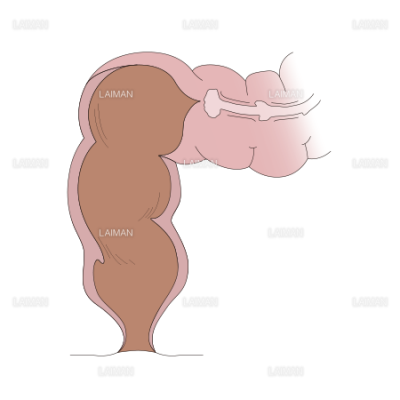

直腸瘤 よくわかる大腸肛門科

直腸脱 よくわかる大腸肛門科

直腸断面 mサイズ Laiman Stockweb メディカルイラスト素材のダウンロード販売

下部直腸の構成図 mサイズ Laiman Stockweb メディカルイラスト素材のダウンロード販売

直腸脱 よくわかる大腸肛門科